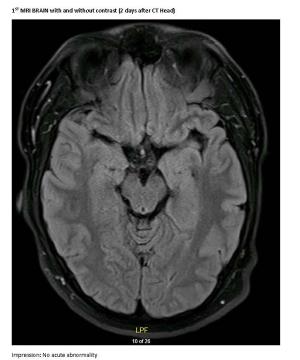

Unusual New Onset Seizures in a Healthy, Young Adult MaleByUma Menon, MD, MBAAugust 21st 2019A 23-year-old male college student presents with first generalized tonic-clonic seizure followed by episodes of violent psychosis.

Case Report: Unusual New Onset SeizuresByUma Menon, MD, MBAAugust 16th 2019A generally healthy, young adult male presents with first generalized tonic-clonic seizure followed by episodes of violent psychosis.